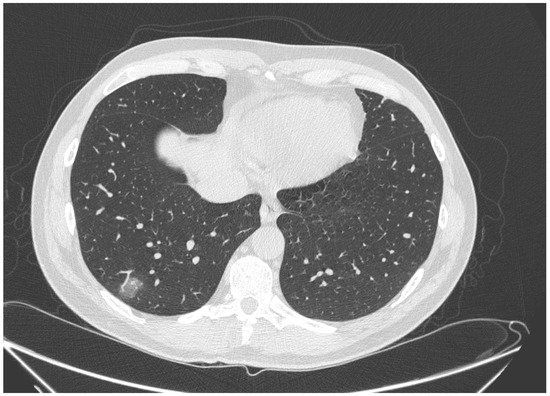

| High diagnostic confidence level | Bilateral multifocal GGO with predominantly peripheral distribution associated or not with septal thickening (crazy paving) and/or consolidations; multifocal GGO of rounded morphology associated or not with crazy paving and/or consolidations; multifocal GGO associated with findings of organizing pneumonia. |

| Intermediate diagnostic confidence level | GGO with diffuse distribution associated or not with crazy paving and/or consolidations; bilateral multifocal GGO and/or consolidations without a prevalent peripheral distribution and without rounded morphology; unilateral GGO with or without consolidation. |

| Low diagnostic confidence level | Isolated small areas of GGO and/or consolidations with non-rounded morphology were included in the low confidence level. |

| Negative for COVID-19 | Cases without the described alterations and with one or more of the following alterations were considered indicative of other diagnoses: isolated lobar or segmental consolidations, presence of solid or caveated nodules, presence of micro-nodules (centro-lobular micro-nodules and “tree in bud” pattern), smooth thickening of the interlobular septa with pleural effusion. |